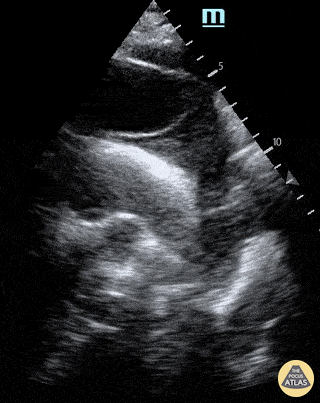

A 65-year-old male presents with shortness of breath (no chest pain) and was found to have a dilated aortic root on CT pulmonary angiogram. POCUS (supra sternal view) showed a dissection flap in the arch of aorta; a finding subsequently confirmed on CT aortagram. Patient was sent for emergency surgical intervention. Dr.Rajasutharsan Kathirgamanathan, Emergency Physician The Northern Hospital, Melbourne, Australia @raj_kathir007